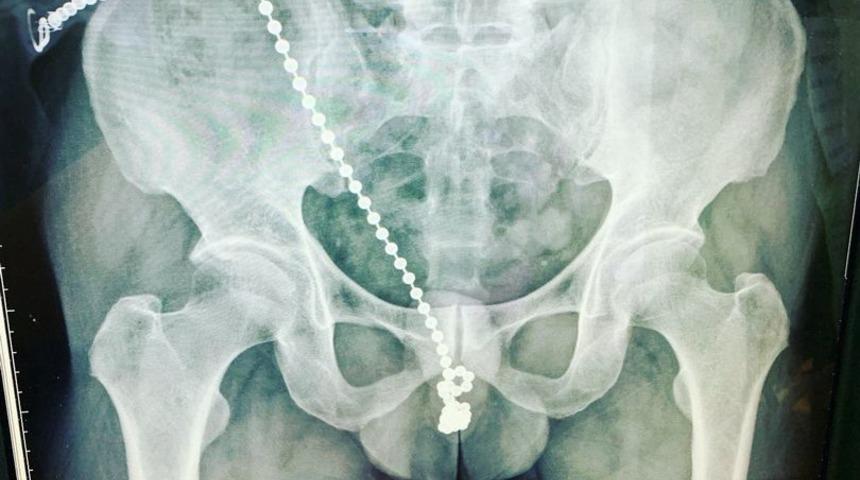

Tayvan’ın New Taipe kentinde 30’lu yaşlarında ismi açıklanmayan bir adam mastürbasyon yaptığı sırada metal boncuklu kolyesinin cinsel organına sıkışması sonucunda kabusu yaşadı. İlginç yönteminin ardından uykuya dalan adam gecenin ilerleyen saatlerinde dayanılmaz bir acıyla uyandı. Kolyesinin boncuklarının cinsel organının içinde olduğunu fark eden adam soluğu acil serviste aldı.

Yeni Taipei'deki Taipei Tıp Üniversitesi Shuang-Ho Hastanesi’nde tedavi altına alınan adamın cinsel organından boncuklar çıkartıldı. Hastayı tedavi eden ürolog Gao Weichang, "Hasta evde zinciri nasıl çıkaracağını bilmiyordu. Zaten yaralanmıştı ve zincirin boncukları da sıkışmıştı. Hasta evde kendi yöntemleriyle boncukları çıkarmaya çalışsaydı tüm idrar yolu hasar görebilirdi” dedi.